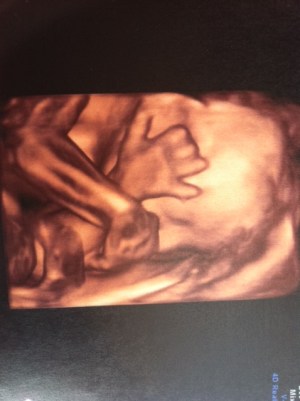

Here are a few of the recent pics (he was being a bit camera shy):